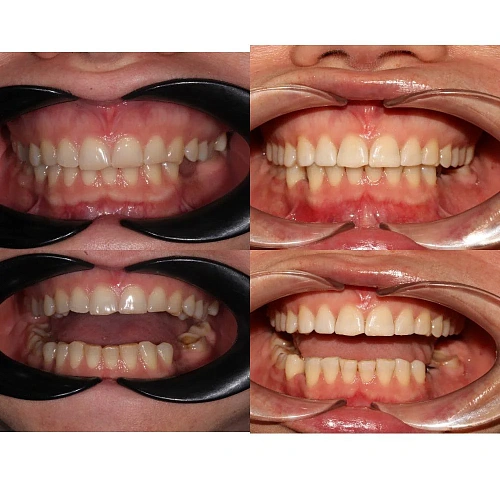

Лечение заняло 28 месяцев (ноябрь 2023 — март 2026). После снятия брекетов пациентка направлена к ортопеду для установки коронок.

Результат

Прикус исправлен, зубы выровнены. Установлены несъёмные ретейнеры на обе челюсти, после установки коронок будут изготовлены ретенционные капы.

Решение: Установили металлические самолигирующие брекеты H4 на обе челюсти. За 28 месяцев выровняли зубы и привели прикус в норму. После снятия брекетов зафиксировали ретейнеры на обе челюсти. Пациентка направлена к ортопеду — в течение недели устанавливает коронки, после чего будет проведено сканирование и изготовлены ретенционные капы уже по окончательному контуру зубов.

Двухэтапный случай: сначала ортодонтия, потом протезирование. Ставить коронки при неправильном прикусе нельзя — нагрузка ляжет неравномерно, конструкции не прослужат долго. Брекеты H4 отработали за 28 месяцев, ряд подготовлен. Ретенционные капы сознательно делаем после коронок — контур зубов изменится, и капы должны соответствовать финальному результату.